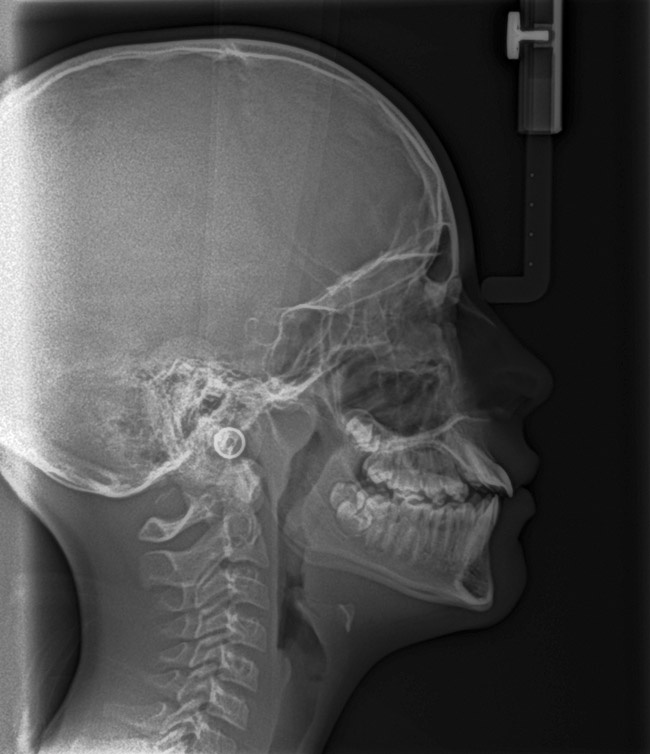

(14.) Angle Class III occlusion with constricted maxilla.

Figure 14

(15.) Cephalometric evaluation demonstrates significant tonsillar blockage of the airway and bimaxillary retursion.

Figure 15